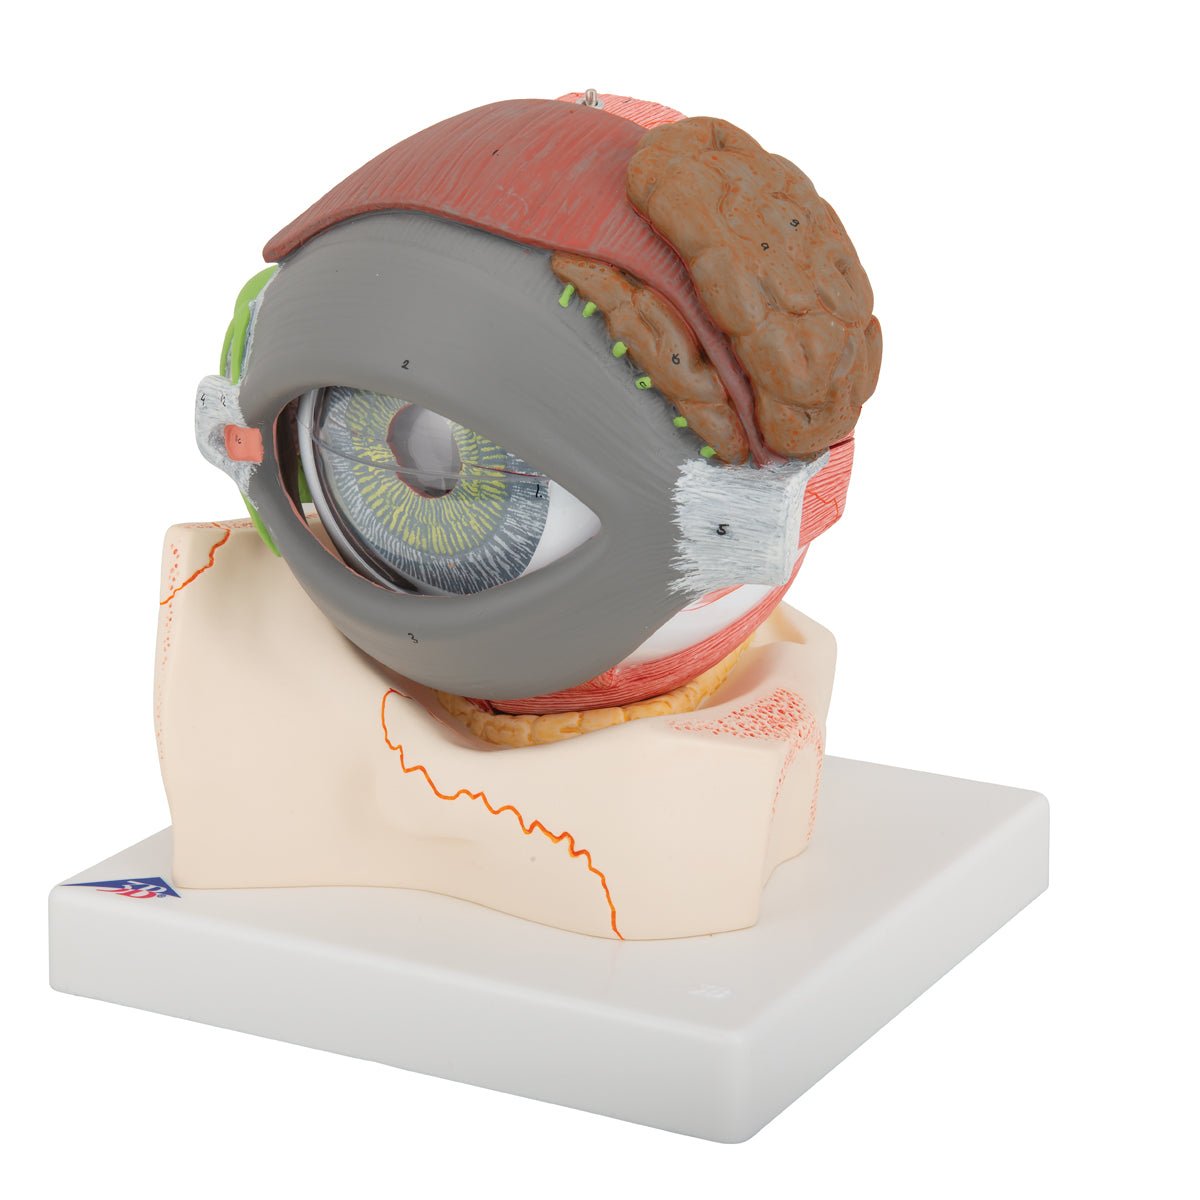

Selling anatomical models is the mainstay of eAnatomi, although we also spend a lot of resources developing our own anatomical materials such as posters. Anatomical models are used for various purposes and can show both defined tissues, organs and organ systems. Are you looking for a simple model of bone tissue or perhaps an advanced torso model based on MRI technology, you can find it all at eanatomi.com.